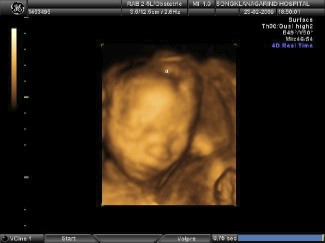

จะว่าไปแล้วการต่อสู้ของทั้งสองเริ่มตั้งแต่วันแรกที่มีการปฏิสนธิเลยทีเดียว ทั้งสองเกิดจากกระบวนการนอกเหนือธรรมชาติที่เรียกว่า IUI ซึ่งเชื้ออสุจิที่สมบูญถูกฉีดส่งเข้าไปในมดลูกโดยตรง ในสภาวะที่รังไข่ถูกกระตุ้นเตรียมพร้อมให้ไข่ตกลงมารอไว้แล้ว ไม่กี่วันหลังจากการฉีดเชื้อก็พบการตั้งครรภ์พร้อม ๆ กับการตกเลือดเล็ก ๆ แต่ก็เพียงพอที่จะทำให้หมอตัดสินใจฉีดฮอโมนกันแท้ง เรากลายเป็นผู้ปวยที่ถูกเรียกรวม ๆ กันว่า ภาวะแท้งคุกคาม ตั้งแต่วันแรก ๆ ที่แฝดทั้งสองเกิดขึ้นมา แต่เราไม่ได้กังวลอะไรมากนักเพราะสภาวะไข่ที่ถูกกระตุ้นมากเกินไปนั้น ความซับซ้อนที่เกิดจากแฝดที่มากกว่าสองคน เช่นแฝดสาม แฝดสี่นั้นน่ากลัวกว่ามาก เราเพียงคิดว่าถ้าเขาทั้งสองคนไม่พร้อมเขาก็จะไม่อยู่กับเราโดยธรรมชาติ ผ่านไปสองเดือนก็แล้วสามเดือนก็แล้ว การตกเลือดไม่มีท่าทีว่าจะหยุด เราถูก admit เข้าโรงพยาบาลหลายต่อหลายครั้ง เกิดภาวะเสียเลือดจนแม่แทบจะเอาตัวไม่รอดอยู่หลายครั้ง จนในที่สุดก็ผ่านวันเวลานั้นมาได้ด้วยคำนิยามใหม่ที่เรียกว่า Ovary rupture แฝดทั้งสองเดิบโตมาในสภาวะที่แม่กำลังดิ้นรนเพื่อจะเอาชีวิตรอด เสียเลือดจนเข้าสู่สภาวะช็อค ธรรมชาติพยายามอย่างดีที่สุดที่จะรักษาชีวิตแฝดเอาไว้ แต่ไม่วายผ่านไป 31 สัปดาห์ น้องสาวซูริ ที่เริ่มโตไม่ทันพี่ชาย ก็มีอาการไม่มีเลือดเข้าไปเลี้ยง ธรรมชาติกำลังตัดสิน แฝดที่พยายามช่วยกันอย่างสุดชีวิตที่จะยื้ออยู่ให้นานที่สุด เพราะถ้าใครคนใดคนหนึ่งยอมแพ้นั่นก็หมายถึงชีวิตของอีกคนเช่นกัน